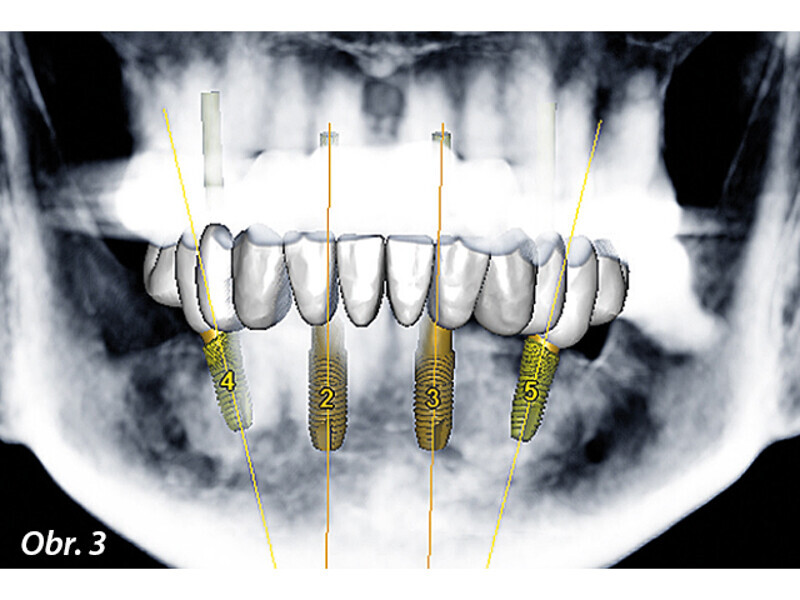

Rekonstrukce chrupu v dolní čelisti